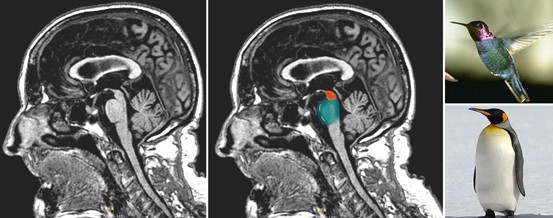

30+ Psp Ziekte. Progressieve supranucleaire parese (psp) is een hersenziekte. Eén op de duizend mensen heeft kans op de ziekte.

Door de afname van dopamine in de hersenen onstaan verschillende klachten als trillen, stijf.

Psp slim and lite (bright); Als ze de ziekte wat langer hebben, kunnen mensen met psp niet meer goed naar boven en naar beneden kijken. De ziekte psp is een vorm van atypisch parkinsonisme. Psp slim (slim and lite);